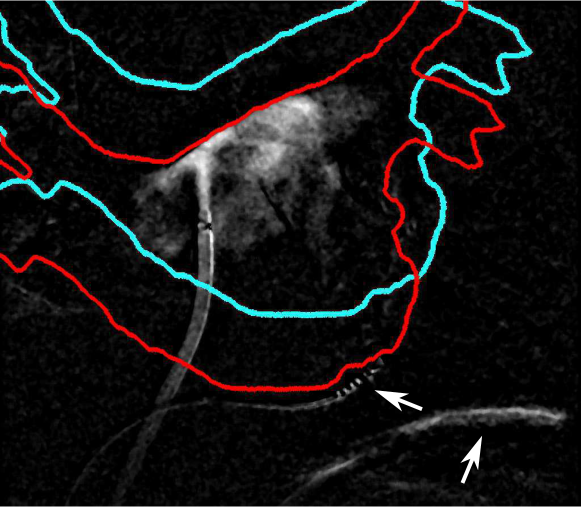

If is chosen suboptimally, the resulting 3-D CADE will be inconsistent with the CA observed in the 2-D images. I.e. a pixel in the 2-D image is constrasted but no corresponding voxel along its projection ray is estimated as contrasted. This can be due to following reasons as shown in Figure 3: (a) the projection ray from a contrasted pixel does not intersect the left atrium as the LA has not been placed at the proper position yet; (b) the projection ray hits the LA, but all voxels intersected by this ray cannot contain CA because their corresponding pixels in the other plane are uncontrasted. Additional inconsistencies are introduced by pixels which are erroneously labeled as contrasted e.g. due to motion artifacts. To verify the validity of the CADE, we compute 2-D images by forward projecting all contrasted voxels in using . We assess the consistency of the CADE for the given transformation by computing the similarity between the fluoroscopic images and the projected CADE by

| (9) |